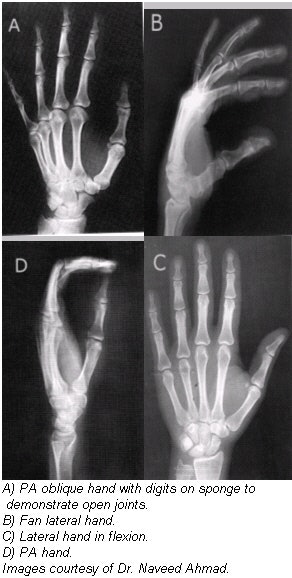

Radiographic examination of the hand is performed using posteroanterior (PA), oblique, and lateral projections. The PA projection is the best conventional view for demonstrating malalignment, joint-space narrowing, and soft-tissue abnormalities in early rheumatoid arthritis, while the anteroposterior (AP) oblique projection ("ball-catcher" position) is commonly used to look for early evidence of rheumatoid arthritis at the second through fifth proximal phalanges and metatarsophalangeal (MP) joints. Both hands are generally exposed, with the contralateral image used for bony structure comparison.

Positioning for PA projection

- Center the cassette to the metacarpophalangeal (MCP) joints, and adjust the long axis of the cassette parallel with the long axis of the hand and forearm.

- Central ray (CR): Perpendicular to the third MCP joint

- The entire hand, wrist, and about 2.5 cm of the distal forearm should be visible.

- MCP and interphalangeal joints should appear open, indicating correct CR location and that hand was fully pronated. The long axis of the hand and wrist should be aligned to the long axis of the IR.

- No rotation of hand as evidenced by the following: the symmetric appearance of both sides or the concavities of the shafts of metacarpals and the phalanges of digits 2 through 5; and the amount of soft tissue on each side of phalanges 2 through 5 appears equal. The digits should be separated slightly with soft tissues and should not be overlapping.

Positioning for PA oblique projection

- Adjust the obliquity of the hand so that the MCP joints form an angle of approximately 45° with the cassette plane.

- Use a 45° foam wedge to support the fingers in the extended position to demonstrate the interphalangeal joints.

- Center the cassette to the MCP joints and adjust the midline to be parallel with the long axis of the hand and forearm.

- CR: Perpendicular to the third MCP joint.

Evaluation criteria

- Entire hand, wrist, and about 2.5 cm of the distal forearm should be visible in oblique view.

- MCP and interphalangeal joints should be open without foreshortening of midphalanges or distal phalanges, indicating fingers are parallel to IR.

- Long axis of hand and wrist should be aligned with IR.

- A 45° oblique is evidenced by the following: Midshafts of third, fourth, and fifth metacarpals should not overlap; some overlap of the distal heads of third, fourth, and fifth metacarpals but no overlap of distal second and third metacarpals should occur; excessive overlap of metacarpals indicates overrotation, and too much separation indicates underrotation.